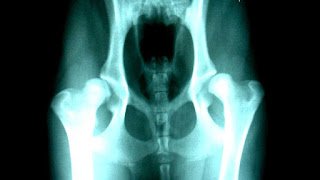

Dogs might exhibit signs of stiffness or soreness after rising from rest, reluctance to exercise, bunny-hopping or other abnormal gait (legs move more together when running rather than swinging alternately), lameness, pain, reluctance to stand on rear legs, jump up, or climb stairs, subluxation or dislocation of the hip joint, or wasting away of the muscle mass in the hip area. Radiographs (X-rays) often confirm the presence of hip dysplasia, but radiographic features may not be present until two years of age in some dogs. Moreover, many affected dogs do not show clinical signs, but some dogs manifest the problem before seven months of age, while others do not show it until well into adulthood.

The classic diagnostic technique is with appropriate X-rays and hip scoring tests. These should be done at an appropriate age, and perhaps repeated at adulthood - if done too young they will not show anything. Since the condition is to a large degree inherited, the hip scores of parents should be professionally checked before buying a pup, and the hip scores of dogs should be checked before relying upon them for breeding. Despite the fact that the condition is inherited, it can occasionally arise even to animals with impeccably hip scored parents.

In diagnosing suspected dysplasia, the x-ray to evaluate the internal state of the joints is usually combined with a study of the animal and how it moves, to confirm whether its quality of life is being affected. Evidence of lameness or abnormal hip or spine use, difficulty or reduced movement when running or navigating steps, are all evidence of a problem. Both aspects have to be taken into account since there can be serious pain with little X-ray evidence.

There are several standardized systems for categorising dysplasia, set out by respective reputable bodies (Orthopedic Foundation for Animals/OFA, PennHIP, British Veterinary Association/BVA). Some of these tests require manipulation of the hip joint into standard positions, in order to reveal their condition on an X-ray.